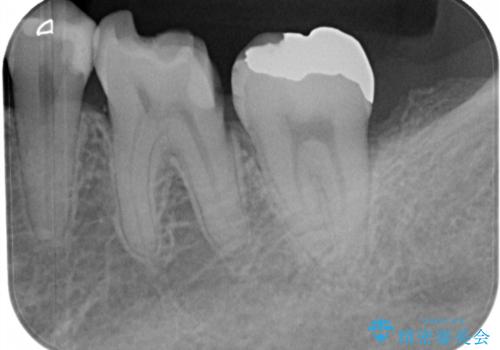

- メタルインレー(保険の金属の詰め物)が取れたとのことで来院された患者様です。

拡大鏡視野下にて、メタルインレーの範囲が大きく虫歯もあったため、オールセラミッククラウンにて修復を行いました。